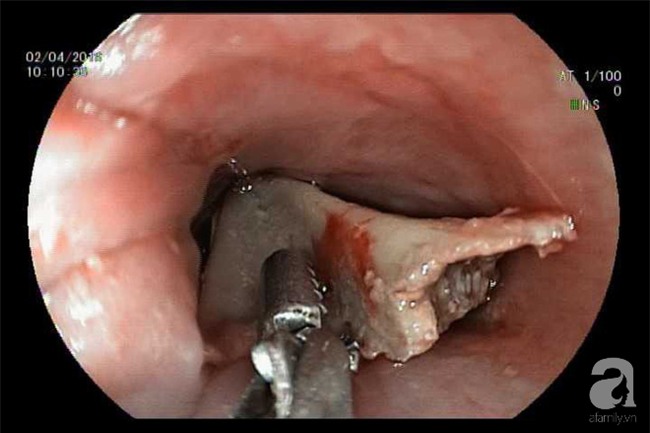

Bệnh nhi nhập viện tại Bệnh viện (BV) Hoàn Mỹ Vạn Phúc 1 trong tình trạng nuốt vướng, đau nhiều vùng hạ họng. Tiến hành thăm khám, chụp X-quang, các bác sĩ phát hiện dị vật tại thực quản đoạn ngang đốt sống cổ C2. Sau khi hội chẩn, ekip điều trị đã tiến hành cho bệnh nhân nội soi thực quản an thần để gắp dị vật.

Thủ thuật gắp dị vật thành công trong 60 phút, lấy ra một mảnh xương đùi gà dài 2,5 cm, rộng 1 cm với bờ nhiều cạnh, sắc nhọn. Nhờ vậy bé gái hết nuốt vướng, không ho khạc ra máu và được xuất viện trong ngày.